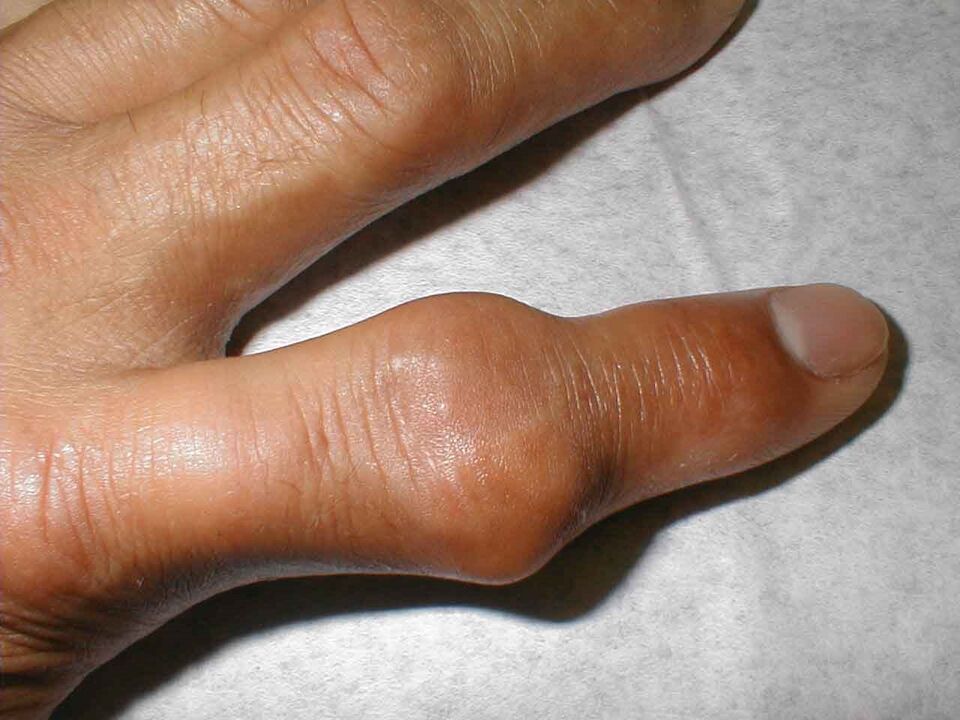

Même au repos, les doigts gonflent et font mal. La douleur survient souvent la nuit. L'apparition de la maladie peut être aiguë, on observe une rougeur des articulations phalangiennes, elles sont chaudes et denses. La température de tout le corps peut augmenter.

La pénétration de la flore bactérienne dans les articulations des doigts peut entraîner une arthrite ou une inflammation des articulations des doigts. Il s'agit le plus souvent de staphylocoques ou de streptocoques. La bactérie provoque une inflammation aiguë caractérisée par un gonflement important des articulations, une rougeur et une augmentation de la température locale.

Les articulations deviennent enflammées et, dans les cas avancés, se déforment à tel point que les doigts perdent complètement leur fonction.

L'articulation grossit et devient rouge. Il est impossible de le toucher et les analgésiques n'aident pas beaucoup. Ce syndrome douloureux sévère est provoqué par l'accumulation de cristaux de sel pointus (urates) dans la cavité articulaire, qui s'enfoncent dans les tissus mous à chaque mouvement et les blessent.

La ligamentite sténosante commence à progresser à la suite d'une inflammation du ligament à la base de l'index. Au fur et à mesure que la maladie progresse, des claquements de doigts se produisent, où la flexion est douloureuse et difficile et l'extension devient presque impossible sans l'aide de la trotteuse. A la base, à l'endroit de la bande enflammée, une formation ronde dense peut être ressentie. Dans ce cas, la douleur peut s’étendre à toute la main et irradier jusqu’au cou. Extérieurement, les doigts semblent bleuâtres et enflés.